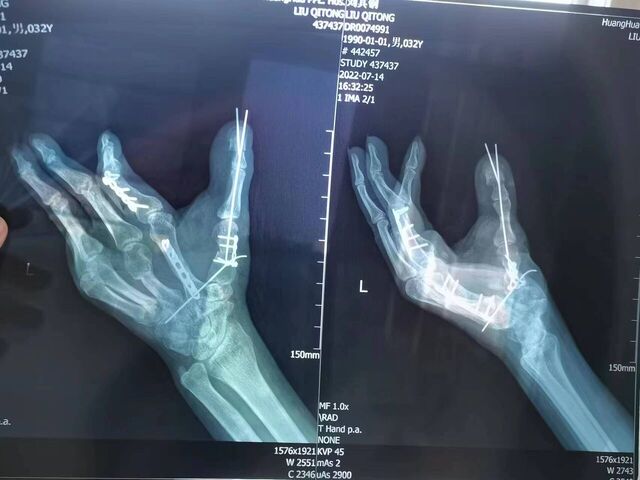

楼主| 发表于 2023-10-22 20:23:58 | 显示全部楼层

拇指再造术后一年半随访

微信图片_20231022194348.jpg 微信图片_20231022194355.jpg 微信图片_20231022194352.jpg 微信图片_20231022194345.jpg 微信图片_20231022194325.jpg 微信图片_20231022194333.jpg 微信图片_20231022194311.jpg 微信图片_20231022194245.jpg 微信图片_20231022194301.jpg 微信图片_20231022194254.jpg 微信图片_20231022193210.jpg 微信图片_20231022193225.jpg 微信图片_20231022193246.jpg 微信图片_20231022193237.jpg 微信图片_20231022194226.jpg 微信图片_20231022194231.jpg